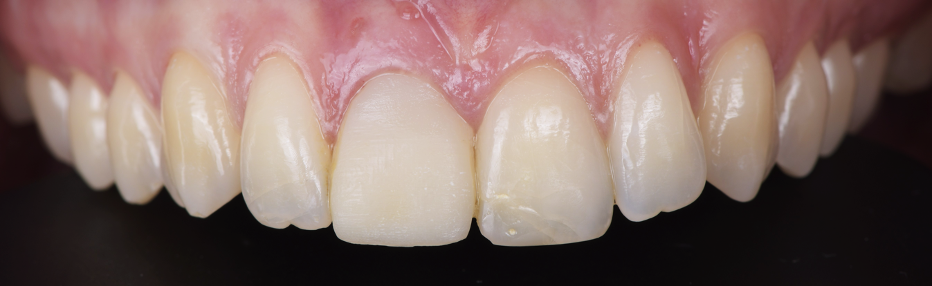

A l’examen clinique on s’aperçoit que la dent 11 est légèrement sur dimensionnée et présente une dyschromie (photo 1).

• La dent 11 présente des dimensions augmentées par rapport à la dent 21 mais reste dans les proportions idéales (Photo 5).